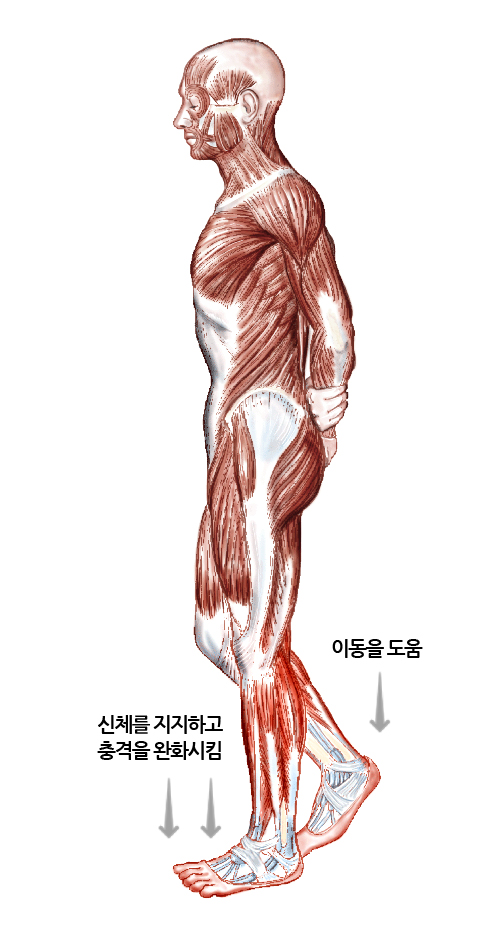

다리의 가장 아래쪽에 있으며 사람이 서있거나 이동할때 바닥을 지지해주는 부분이며, 주로 우리 몸의 이동과 관련된 역할을 합니다.

다리의 가장 아래쪽으로 사람이 섰을때 바닥을 지지하는 부분입니다.

발은 우리가 서있을때 우리 몸을 지탱해주고 걷거나 운동할때 이동을 도와주는 역할을 합니다. 또한 발의 아치 구조는 걷거나 달릴때 발생하는 충격을 완화시켜줍니다.